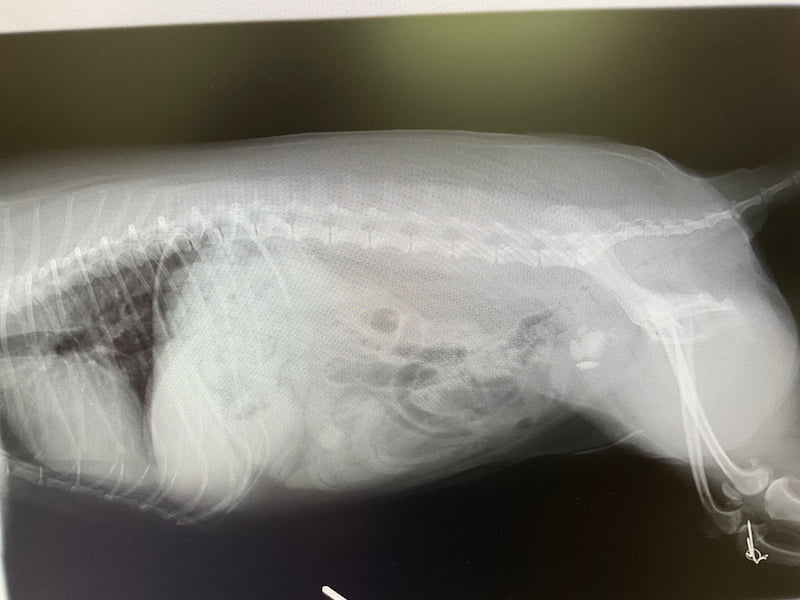

尿中の細菌、真菌、原虫などの病原微生物の存在の有無を光学顕微鏡で観察します。細菌や真菌であれば薬剤感受性試験を行い、適切な抗菌薬や抗真菌薬の投与に役立ちます。 - X線検査

腎臓の形状やサイズ、尿路結石や前立腺のサイズや形状の評価をするために、腹部X線検査が行われます。 - 造影X線検査